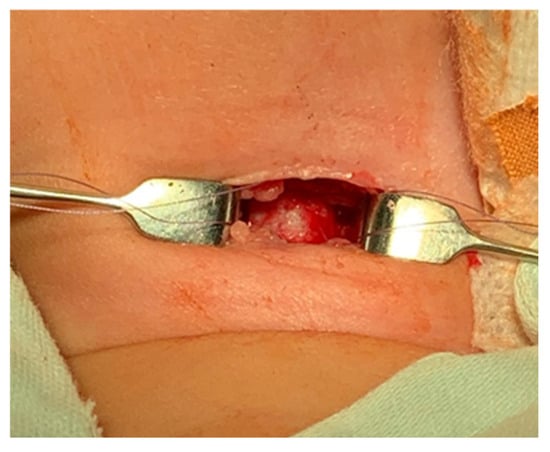

- The platysma is reached, and its muscles are separated and retracted using retractors (Figure 3).

- Bipolar cautery is used during the procedure for hemostasis (Figure 4).